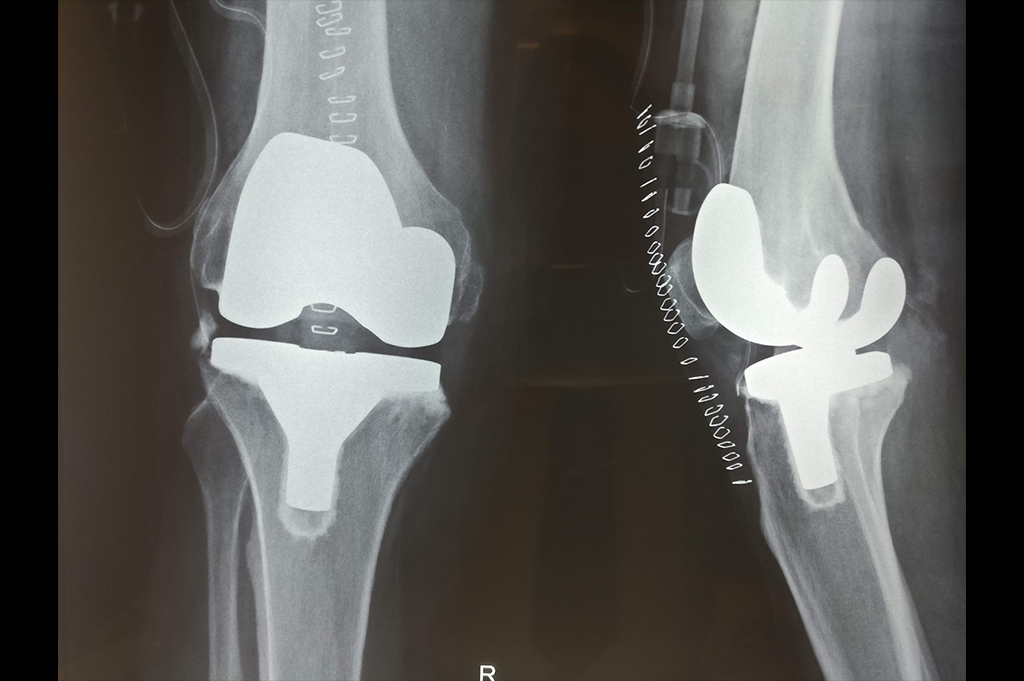

Total Knee Replacement - TKR